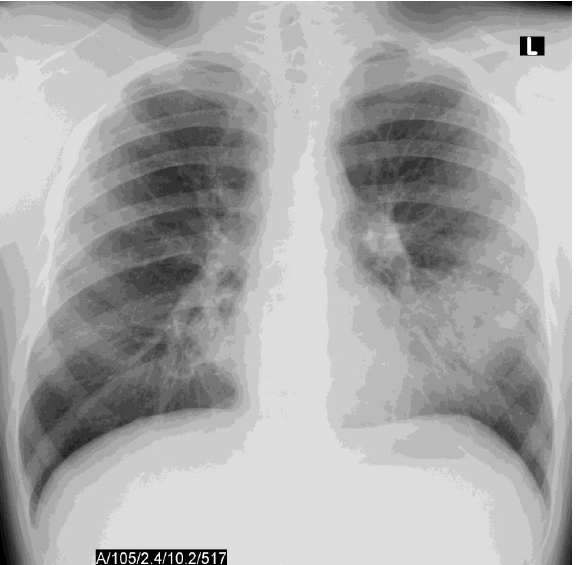

מהו הממצא הטיפוסי לתמונה

פניאומוקוק- רואים לובולר פניאומוניה Typical pneumonia